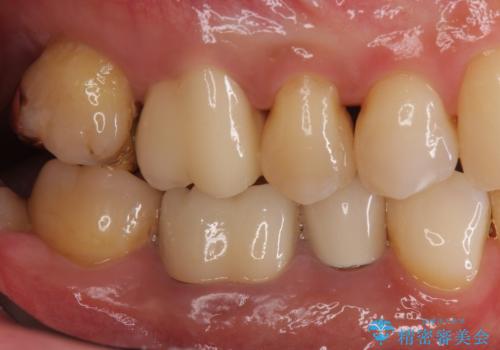

- 銀歯をすべてやり替えたいとのことで来院された患者様です。

再根管治療が必要なところは再根管治療から、そうでないところは補綴物のみをやり替えていくこととなりました。

銀歯のやり替えと並行してホワイトニングも行いました。

結果的には銀歯がすべて白くなり、前歯のガタつきもある程度改善され大変喜んでいただけました。